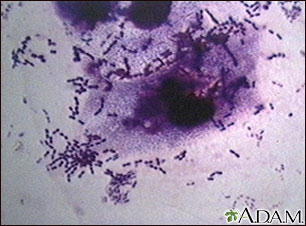

Bacteria, viruses, parasites, and other germs (microbes) cause many human diseases. Vaccines can help protect against some of these diseases.

Bacteria, viruses, parasites, and other germs (microbes) cause many human diseases. Vaccines can help protect against some of these diseases. Vaccination (immunization) against infectious diseases saves millions of lives. Illness and death from diphtheria, pertussis, tetanus, measles, mumps, hepatitis, and other diseases can be prevented through immunization.